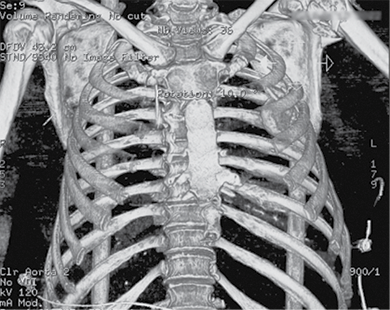

Figure 2. Subsequent 3D reconstruction

A 58-year-old patient was admitted to the Emergency Department of level I Trauma Center in August 2022 due to polytrauma sustained in a car accident. On arrival, the patient’s condition was severe, with decreased consciousness (GCS score of 12), unstable hemodynamic, subcompensated peripheral circulation, blood pressure of 62/32, and heart rate of 78 beats per minute. There was reduced breathing on the left side with a respiratory rate of 18 breaths per minute and an oxygen saturation (SpO2) of 85.0%. Palpation revealed pain in the left posterior chest. X-rays and CT scans were performed, which revealed a traumatic hemothorax on the left side, humeral head within the pleural cavity, three rib fractures, lung contusion, and hematoma.

Neurovascular status of the left hand was intact. The patient’s condition was stabilized in the intensive care unit and after 5 days transferred to the Thoracic Surgery Department, where 4 days later a resection of the fifth rib, thoracoscopic removal of the humeral head, and lung decortication were performed.